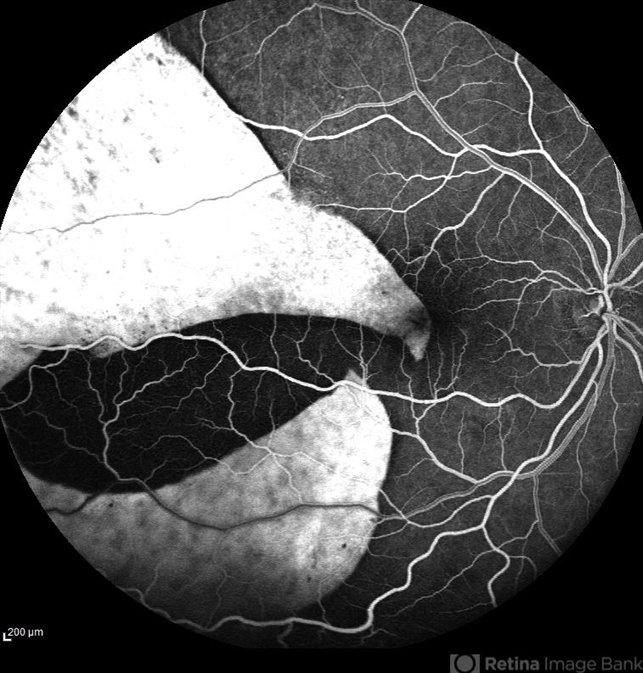

- RPE-Rip

Scanning laser ophthalmoscope

Heidelberg HRA - Description

- Fundus fluorescein angiography of a 50 year-old patient with spontaneous giant RPE rip.